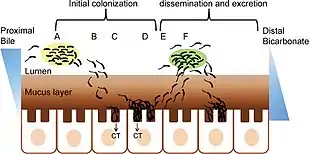

When consumed, most bacteria do not survive the acidic conditions of the human stomach.[31] The few surviving bacteria conserve their energy and stored nutrients during the passage through the stomach by shutting down protein production. When the surviving bacteria exit the stomach and reach the small intestine, they must propel themselves through the thick mucus that lines the small intestine to reach the intestinal walls where they can attach and thrive.[31]

Once the cholera bacteria reach the intestinal wall, they no longer need the flagella to move. The bacteria stop producing the protein flagellin to conserve energy and nutrients by changing the mix of proteins that they express in response to the changed chemical surroundings. On reaching the intestinal wall, V. cholerae start producing the toxic proteins that give the infected person a watery diarrhea. This carries the multiplying new generations of V. cholerae bacteria out into the drinking water of the next host if proper sanitation measures are not in place.[32]

The cholera toxin (CTX or CT) is an oligomeric complex made up of six protein subunits: a single copy of the A subunit (part A), and five copies of the B subunit (part B), connected by a disulfide bond. The five B subunits form a five-membered ring that binds to GM1 gangliosides on the surface of the intestinal epithelium cells. The A1 portion of the A subunit is an enzyme that ADP-ribosylates G proteins, while the A2 chain fits into the central pore of the B subunit ring. Upon binding, the complex is taken into the cell via receptor-mediated endocytosis. Once inside the cell, the disulfide bond is reduced, and the A1 subunit is freed to bind with a human partner protein called ADP-ribosylation factor 6 (Arf6).[33] Binding exposes its active site, allowing it to permanently ribosylate the Gs alpha subunit of the heterotrimeric G protein. This results in constitutive cAMP production, which in turn leads to the secretion of water, sodium, potassium, and bicarbonate into the lumen of the small intestine and rapid dehydration. The gene encoding the cholera toxin was introduced into V. cholerae by horizontal gene transfer. Virulent strains of V. cholerae carry a variant of a temperate bacteriophage called CTXφ.

Microbiologists have studied the genetic mechanisms by which the V. cholerae bacteria turn off the production of some proteins and turn on the production of other proteins as they respond to the series of chemical environments they encounter, passing through the stomach, through the mucous layer of the small intestine, and on to the intestinal wall.[34] Of particular interest have been the genetic mechanisms by which cholera bacteria turn on the protein production of the toxins that interact with host cell mechanisms to pump chloride ions into the small intestine, creating an ionic pressure which prevents sodium ions from entering the cell. The chloride and sodium ions create a salt-water environment in the small intestines, which through osmosis can pull up to six liters of water per day through the intestinal cells, creating the massive amounts of diarrhea. The host can become rapidly dehydrated unless treated properly.[35]

By inserting separate, successive sections of V. cholerae DNA into the DNA of other bacteria, such as E. coli that would not naturally produce the protein toxins, researchers have investigated the mechanisms by which V. cholerae responds to the changing chemical environments of the stomach, mucous layers, and intestinal wall. Researchers have discovered a complex cascade of regulatory proteins controls expression of V. cholerae virulence determinants.[36] In responding to the chemical environment at the intestinal wall, the V. cholerae bacteria produce the TcpP/TcpH proteins, which, together with the ToxR/ToxS proteins, activate the expression of the ToxT regulatory protein. ToxT then directly activates expression of virulence genes that produce the toxins, causing diarrhea in the infected person and allowing the bacteria to colonize the intestine.[34] Current research aims at discovering "the signal that makes the cholera bacteria stop swimming and start to colonize (that is, adhere to the cells of) the small intestine."[34]